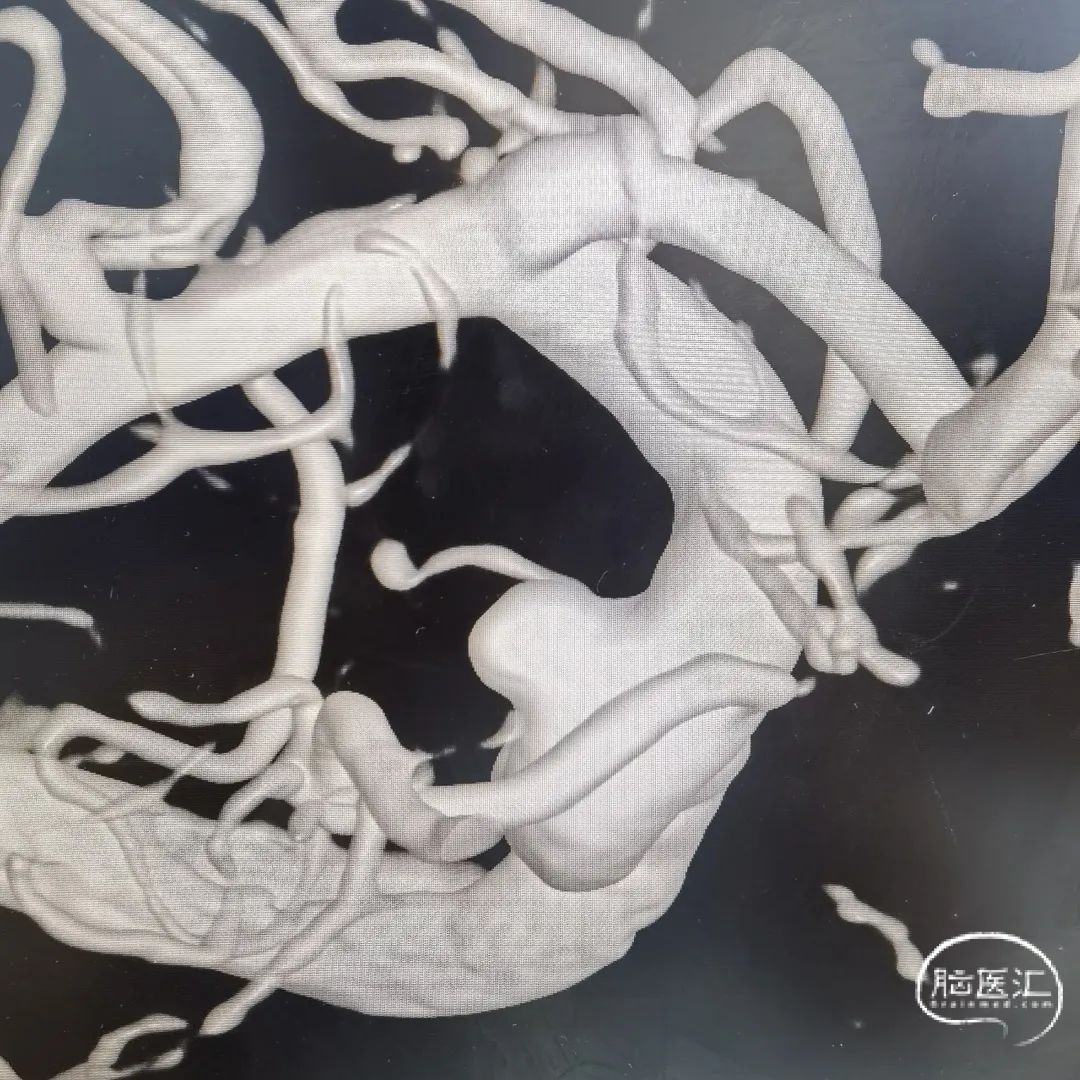

这是一根115cm 通桥银蛇®颅内支持导管,通过R-DAS技术非常容易地放置到海绵窦段,手术过程中实际到达了海绵窦段后膝的位置,在这样的情况下释放血流导向装置就非常容易。

6F 115cm 通桥银蛇®颅内支持导管 。

FD